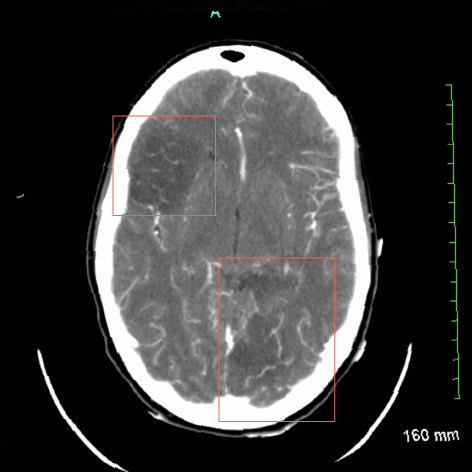

Cortical Strokes

• Most common finding (Cortically-based MCA strokes being the most common).

• Hemorrhagic conversion is common and complicates any use of anticoagulants/anti-thrombotics.